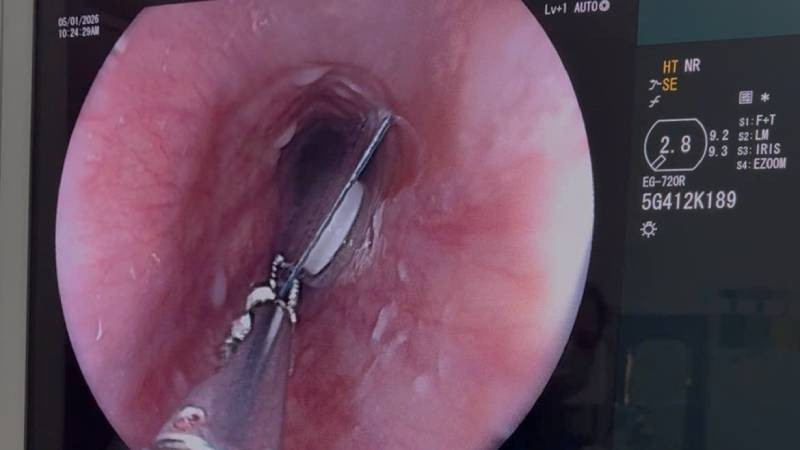

Quảng Trị: Kịp thời lấy viên thuốc nguyên vỏ bao kẽm kẹt ngang thực quản người bệnh

Thứ Tư, ngày 07/01/2026 02:38Ngày 6/1, Bệnh viện Hữu Nghị Quảng Bình, tỉnh Quảng Trị cho biết, vừa xử trí thành công 1 trường hợp bị dị vật thực quản đặc biệt, là viên thuốc còn nguyên trong bao kẽm. Dị vật gây đau...